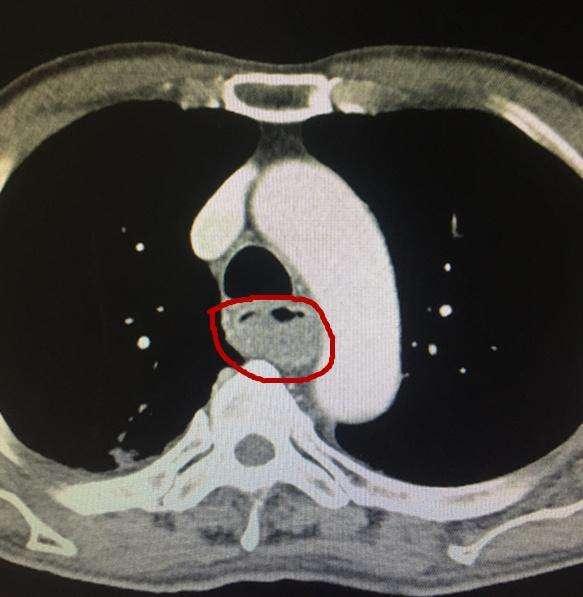

(3)食管

胸部CT还可以看食管有没有问题,例如食管有没有异物,例如卡鱼刺,鸡骨头等等,有没有食管憩室,食管癌等等,可以了解肿瘤侵犯食管的范围,有没有淋巴结转移,大血管有没有受到侵犯等等。

食管癌